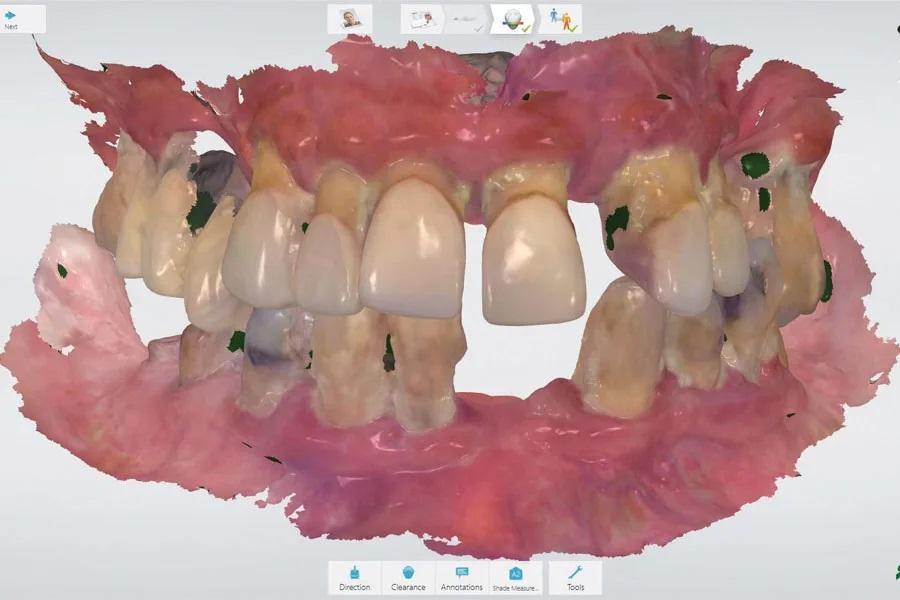

Цифровые технологии позволяют ускорить лечение: все зубы удаляются за один визит, и протезы устанавливаются сразу. С помощью внутриротового сканера (TRIOS) были отсканированы зубы и ткани, а также зарегистрирован прикус (Фото 3). По цифровому протоколу CAD/CAM (3Shape) были изготовлены протезы с укороченными границами. Вся информация об окклюзионной высоте и положении зубов была получена из 3D-сканирования и регистрации прикуса на первом визите. Клинические данные и фотографии были отправлены в лабораторию. Через две недели все зубы были удалены (Фото 4 и Фото 5), и пациентке установили протезы с мягкой подкладкой (COE-SOFT) (Фото 6).

Фото 3: Сканирование зубов, тканей и регистрация прикуса.